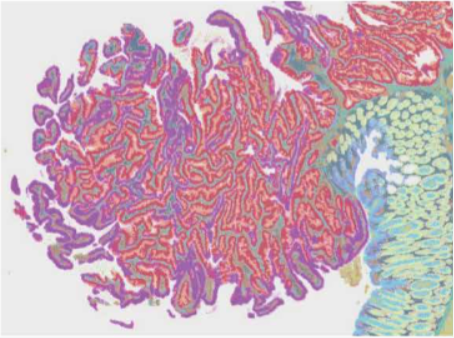

▲通过 Visium CytAssist 实现精准的转录本定位

▲通过高分辨率的空间转录组学来增强 H & E 或 IF 成像后的样本。

▲兼容 H & E 染色以及 IF 染色 Visium HD 空间基因表达兼容 H &E 染色以及 IF 染色。

(可在同一组织切片上进行高分辨率空间转录组学数据分析)